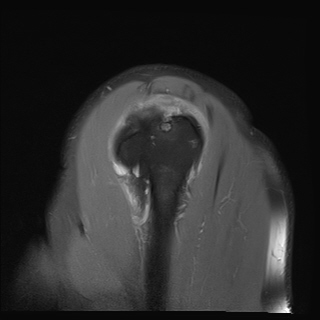

±Ø»ó°Ç ±ÙÀ§ºÎ ±Ø»ó°Ç ³»ÃøÀÇ Àú¿¡ÄÚ ºÎÁ¾°ú Á¡¾×³¶ ºÎÁ¾ÀÌ °üÂûµÊ(±×¸² 5).

±Ø»ó°Ç ÆÄ¿­, Á¡¾×³¶¿°, °ßºÀÇÏ °ñ±Ø